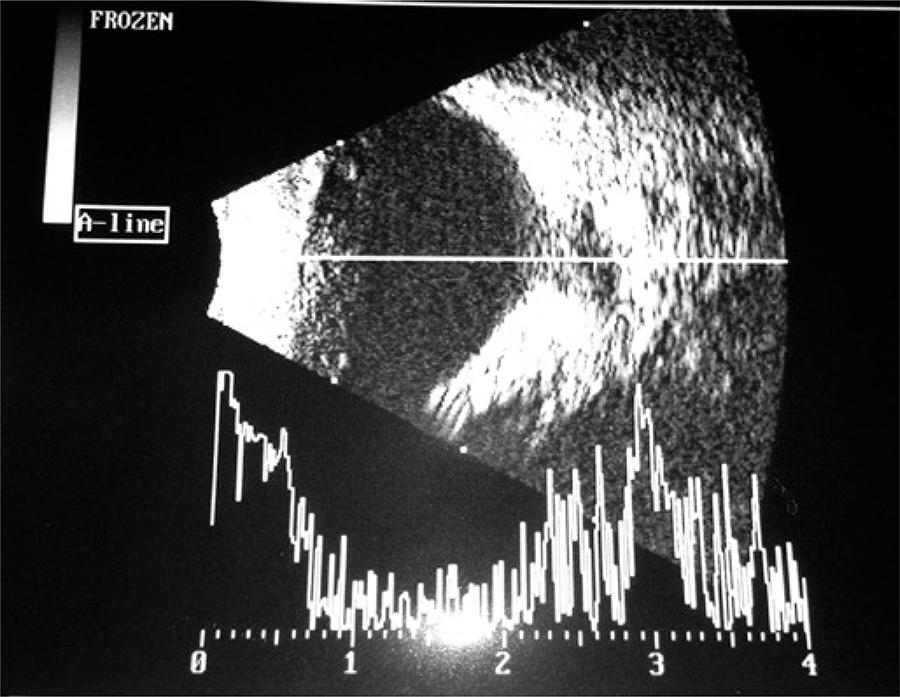

A 6-year-old patient was referred to our ophthalmology service because of an ocular deviation (esotropia) on the right eye for 3 years. Best-corrected visual acuity in right eye and 20/20 in left eye. According to the Krimsky test, the patient showed 15 prism dioptres esotropia in right eye. No changes were observed in biomicroscopy of both eyes and funduscopy of left eye was normal. An optical disc of increased size was seen in right eye, covered by glial tissue, rectified retinal vessels and with radial distribution. To confirm the diagnosis, we conducted an echography that showed typical sclerotic defect of Morning Glory syndrome, which is an increase of optic disc excavation and peripapilar retina ( and ).